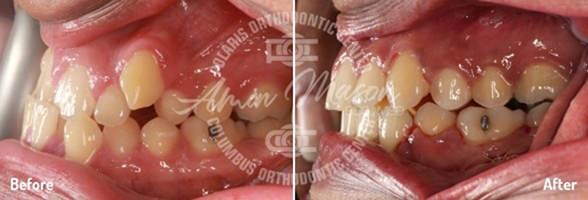

Case 7

An adult male patient presented to our office with a deep bite, crowding, and tooth wear. The patient exhibited class II molar occlusion, severe deep bite, and maxillary/mandibular crowding. The patient was treated with class II corrector and limited maxillary braces for a short time and was transitioned to Invisalign clear aligners. Patient achieved fantastic results and was very satisfied with the results. Treatment time: 22 months.